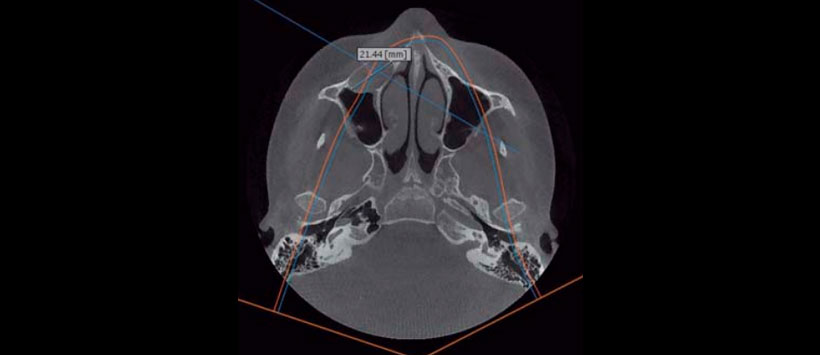

Imagenológicamente en la ortopantomografía se observó una zona radiolúcida unilocular circunscrita bien delimitada, con borde radiopaco bien definido, segundo premolar incluido en posición horizontal. Segundo molar deciduo con tratamiento pulpar. Tomografía de haz cónico: cortes axiales, sagitales, coronales y reconstrucción tridimensional mostraron quiste maxilar derecho de 2.6 cm de diámetro total, ocupando la tercera parte de la capacidad volumétrica de seno maxilar, desplazamiento de la pared anterior de seno maxilar y pared lateral de la fosa nasal derecha (Figuras 4 a 6).